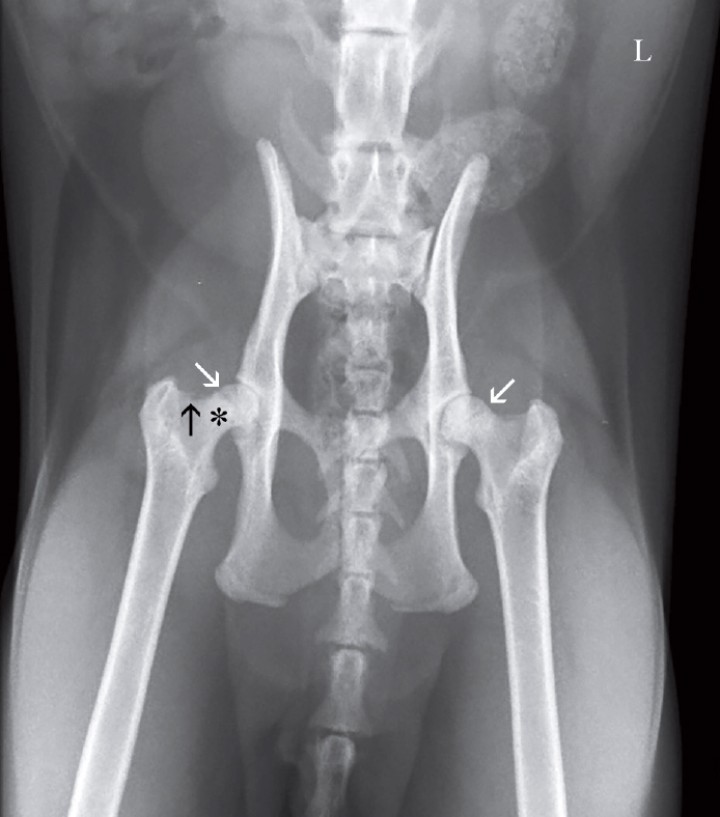

En ambas extremidades se observa una línea radiotransparente en la cabeza femoral, más evidenciable en la extremidad derecha, correspondientes al cartílago de crecimiento de la cabeza femoral. Además, en el cuello femoral derecho se visualiza osteofitosis y pequeñas áreas osteolíticas. Los cartílagos de crecimiento de las tuberosidades isquiáticas y la sínfisis pélvica permanecen sin fusionar (Fig. 2).

<p>Misma imagen que la Figura 1. Se aprecia en ambas extremidades una línea radiotransparente en la cabeza femoral, correspondientes al cartílago de crecimiento de la cabeza femoral (flechas blancas). En el cuello femoral derecho se visualizan osteofitos (flecha negra) y pequeñas áreas osteolíticas (asterisco). Los cartílagos de crecimiento de las tuberosidades isquiáticas y la sínfisis pélvica permanecen sin fusionar. L: izquierda.</p>

Figura 2

Misma imagen que la Figura 1. Se aprecia en ambas extremidades una línea radiotransparente en la cabeza femoral, correspondientes al cartílago de crecimiento de la cabeza femoral (flechas blancas). En el cuello femoral derecho se visualizan osteofitos (flecha negra) y pequeñas áreas osteolíticas (asterisco). Los cartílagos de crecimiento de las tuberosidades isquiáticas y la sínfisis pélvica permanecen sin fusionar. L: izquierda.